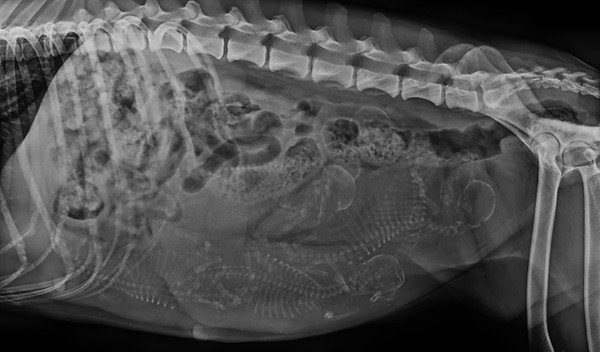

30.09.2025 (Tag 54): Wir waren zum röntgen und somit wissen wir jetzt, wie viele Welpen nächste Woche erwartet werden.